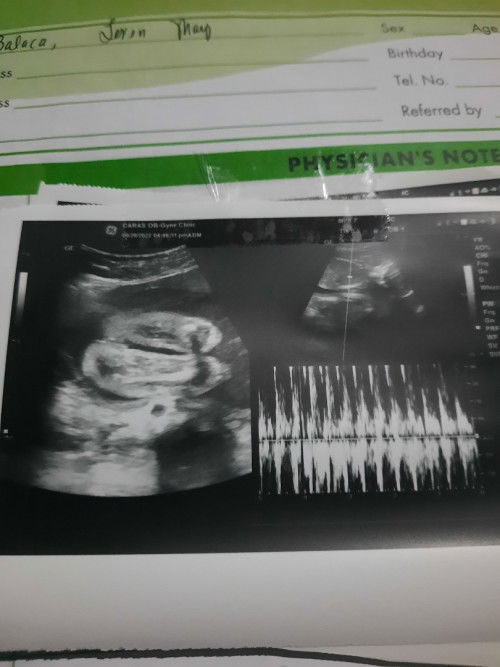

#pleasehelp baby girl po ba ito or boy base sa picture? 90% sure daw po kasi si doc na girl sya eh hehe. Ano po sa tingin nyo mga mi?

#pleasehelp mga mi pag 90% sure po ba sa gender si doc sure na sure na ba yun? 90% sure daw po kasi syang girl ang baby ko hehe. Ano sa tingin nyo base sa picture po girl po ba talaga? :)